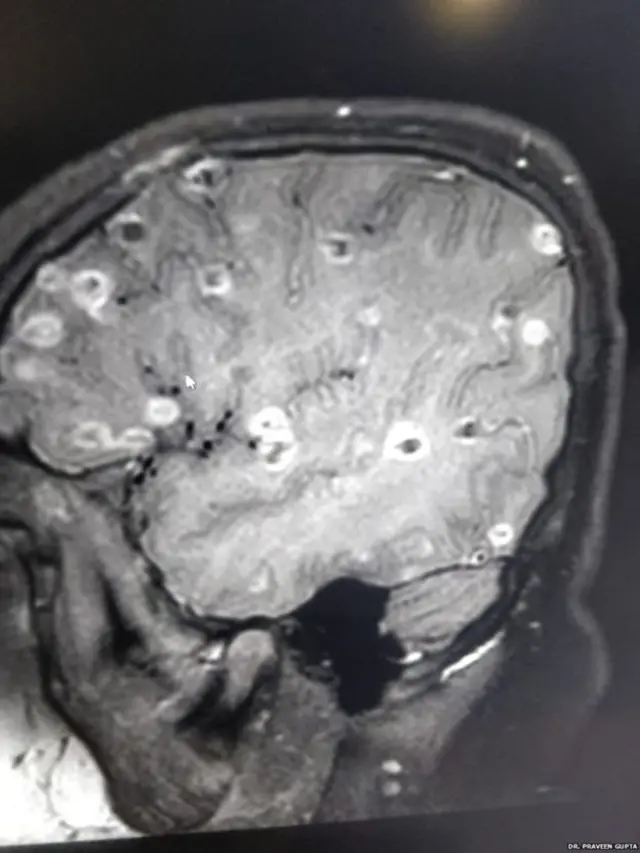

"மருத்துவமனைக்கு கொண்டுவரப்பட்டபோது சிறுமி மயக்கநிலையில் இருந்தார். அவரது மூளையில் நூற்றுக்கணக்கான வெண்ணிற புள்ளிகள் இருப்பதை சி.டி ஸ்கேன் காட்டியது. அவை என்ன தெரியுமா? நாடாப்புழுவின் முட்டைகள்."

டாக்டர் குப்தாவிடம் வரும்போது,சிறுமிக்கு ரத்த அழுத்தமும் அதிகமாக இருந்தது. நாடாப்புழுக்கள் கொடுத்த அழுத்தம் மூளையை பாதித்து, மூளையின் செயல்பாட்டை நிறுத்திவிட்டது.

பட மூலாதாரம், DR PRAVEEN GUPTA

"முதலில் மருந்துகள் கொடுத்து மூளையின் அழுத்தத்தை குறைத்தோம். (மூளைக்குள் வெளிப்புற பொருட்கள் ஏதாவது வந்தால் அது மூளையின் உட்புற சமநிலையை குறைக்கிறது). பின்னர், மூளையில் கட்டிகளைப்போல் இருந்த முட்டைகளை கொல்ல மருந்து கொடுத்தோம். இது நிலைமையை மோசமாக்கும் அபாயமும் இருந்தது. ஏனெனில் இந்த சமயத்தில் மூளைக்கு அழுத்தம் அதிகரிக்கும் வாய்ப்புகள் அதிகம்."

மூளையில் உள்ள நாடாப்புழுவின் முட்டைகளை கொல்லும் மருந்து சிறுமிக்கு கொடுக்கப்பட்டாலும், அவை இன்னும் முற்றிலுமாக அழியவில்லை. அவை கொஞ்சம் கொஞ்சமாகத்தான் அழியும்.

மூளையில் இந்த முட்டைகளின் எண்ணிக்கை தொடந்து அதிகரித்துக் கொண்டேயிருக்கும். இது வலிப்பு வருவதற்கும் முக்கிய காரணமாகிறது என்கிறார் டாக்டர் குப்தா.